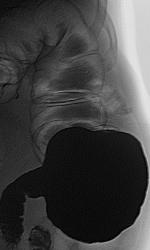

Выложил более информативные сканы. ваше мнение?

Ну "перво - наперво" шикарно видно "сужение"

Это исследование я проводил сегодня утром, помимо данного участка с "органикой" есть ещё один участок, который отчётливо видно на МСКТ при анализе изображений, но почему то мой более старший коллега ни стал об этом указывать ссылаясь на то, что преригатива скопического и эндоскопического исследований, у нас там конечно ни шуточная баталия разгорелась, и вообще поставил данный участой симметричного сужения подвопросом:

Именно этим мне и показался данный случай интересным, получается именно данный участок видели эндоскописты, а это участок поперечного отдела ободочной кишки, даже почти селезёночный угол, чётко видно на МСКТ. И получается что первично-множественный рак толстого кишечника, если я не прав поправте меня.

То что в нисходящем отделе ободочной кишки-дивертикулез это на 100%, по поводу "сигмы" ещё можно посомниваться, но этот участок попадает под резекцию, у морфологов узнаю, а вот ампула прямой кишки, это да, что как то я сомневаюсь до сих пор что это остаточные каловые массы, пациент подготовлен-отлично, возможно полип, но как бы ещё хуже не оказалось, но в дальнейшем всё равно попадёт к нам на контроль, плюс эндоскописты. Кстати вроде планы ещё резко сменились по ведению этого пациента, думаю хирурги озадачились, хотя трансфузиолог свои запеси уже оставил.

Описание операции: ЭТН. Срединная лапаротомия. При ревизии в селезеночном углу толстой кишки циркулярная опухоль до 10 см диаметром, в проксимальной трети сигмовидной кишки блюдцеобразная опухоль до 5 см диаметром, заниающая 1/2 окружности кишки, долихосигма. В печени, забрюшинном пространстве, желудке, тонкой кишке патологии не выявлено, желчный пузырь ранее оперативно удален. Мобилизована сигмовидная, нисходящая, поперечноободочная кишка до правой ветви средней толстокишечной аретрии, выполнена левосторонняя гемиколэктомия. Сформирован трансвенрзо-сигмоанастомоз 2-рядным узловым швом. Дефект брыжейки ушит. Гемостаз. Счет салфеток. Трубчатый дренаж в левый боковой канал. Послойные швы на рану.

Описание препарата Удаленная левая половина толстой кишки длиной до 1,2 м с опухолью до 10 см диаметром, циркулярно суживающей просвет и опухолью до 5 см диаметром, блюдцеобразной занимающей 1\2 окружности кишки. В среденй трети сигмовидной кишки дивертикул до 1 см диамером.